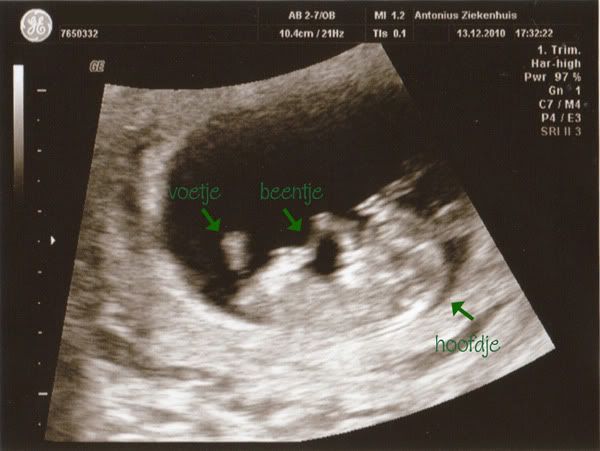

Gisteren eindelijk de eerste echo gehad!

Alles was in orde en de kleine loopt goed op schema. Ze schatten het op 6 juli 2011, 1 dagje later dus...

De kleine werd zelfs nog ff wakker op een gegeven moment, dus hebben het ook nog zien bewegen...

Hieronder nog ff een fotootje.